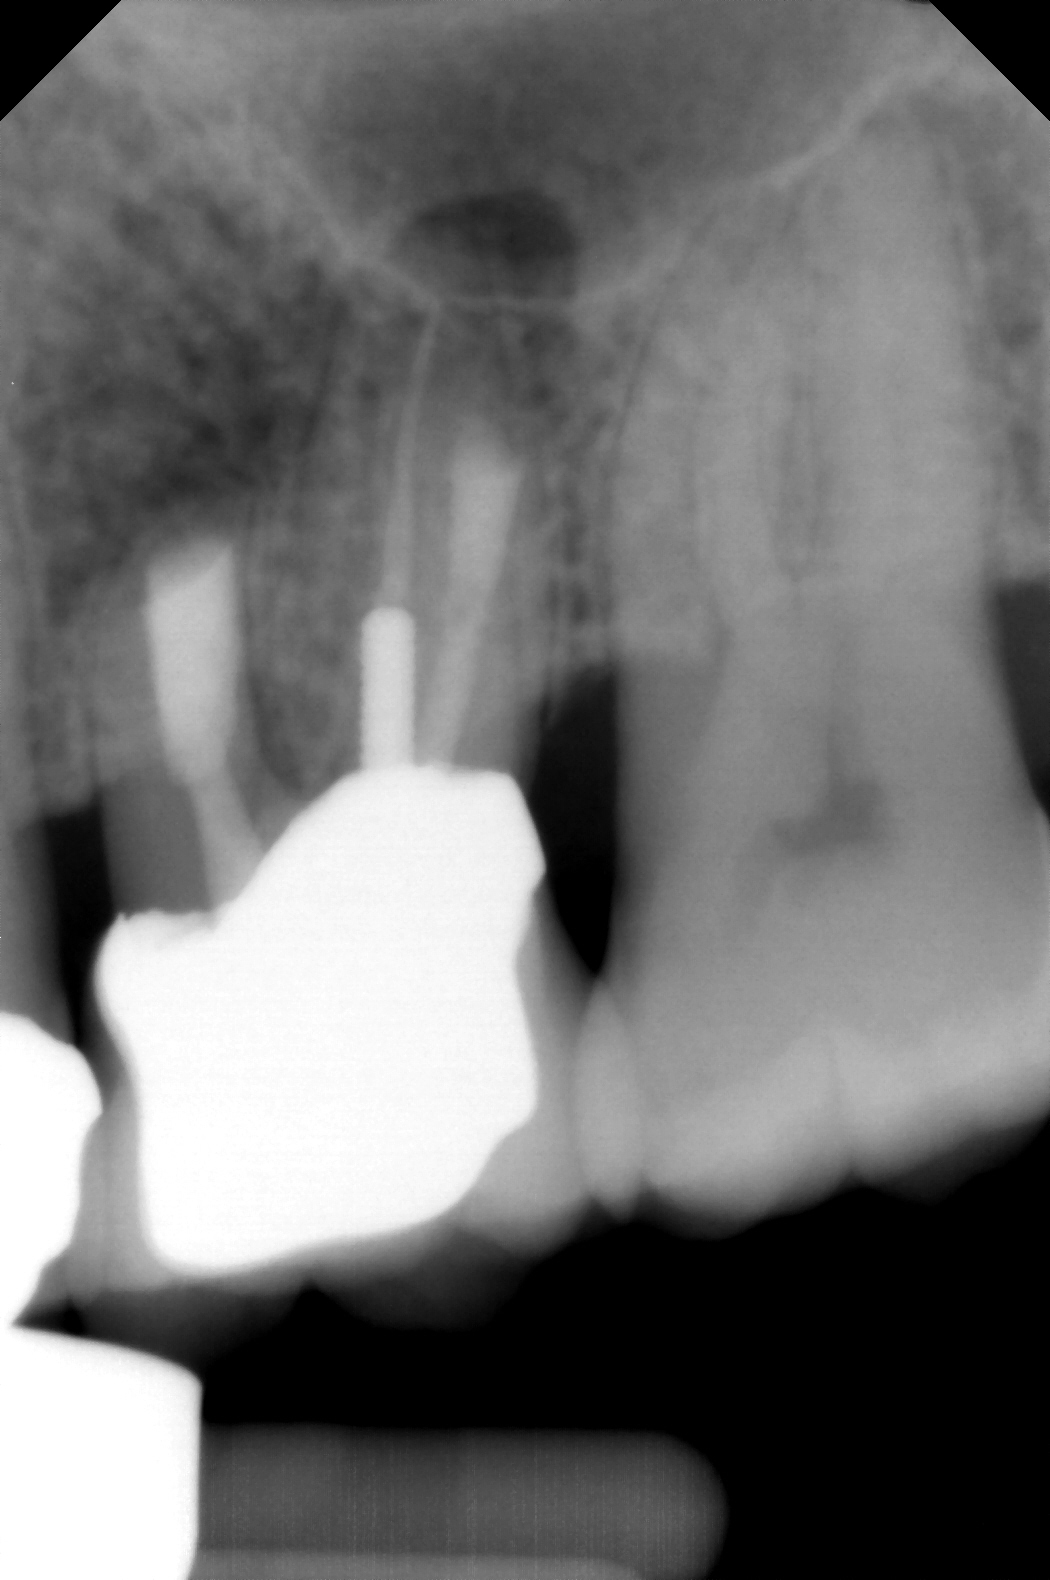

Fig 5. Working length confirmation.

Figure 5

Fig 6. Postoperative radiograph.

Figure 6

Clinical procedure: Regeneration of the endodontic pulp space is indicated for cases with very thin dentinal walls and an open apex that is more than 1 mm in diameter radiographically (Figure 4). Disinfection of the root canal system is performed using sodium hypochlorite irrigation followed by a triple antibiotic paste dressing that is left in place for 1 week. At the second visit, ethylenediaminetetraacetic acid (EDTA) is used to condition the dentin walls, which results in the release of growth factors, and bleeding is stimulated in the periapical tissues (where stem cells are located), with the aim of filling the pulp space with a stable blood clot, which would serve as the scaffold. MTA is then placed at the canal orifice in contact with the clot to protect it from coronal microleakage (Figure 5 and Figure 6). In time, the clot should be replaced with a reparative tissue of variable composition, and the root walls should continue to thicken due to the deposition of a dentin-like material on the pre-existing root dentin27,28 (Figure 7 and Figure 8).